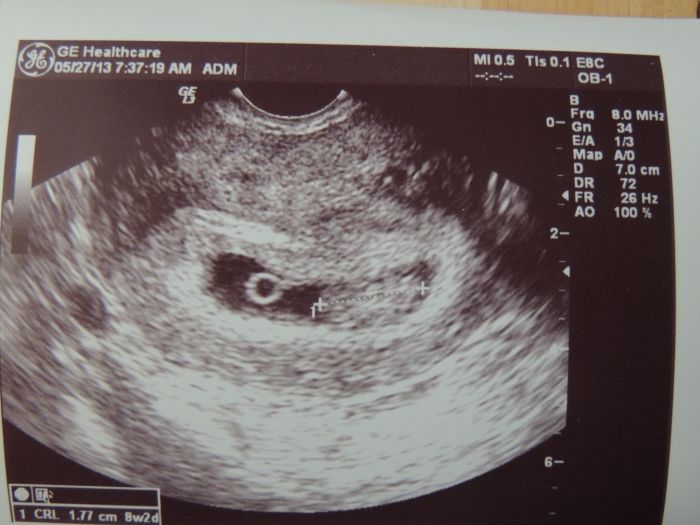

Ahoj holky, tak jsem byla na druhém ultrazvuju. Jsme v pondělí podle MS i podle US 8+2. Termín ještě nemám, ale zatím to podle výpočtů vypadá na přelom roku. Zatím to vypadá, že je všechno jak má být. Akorát jsem teda nervózní, když mě přestanou bolet prsa. To je skoro jediný těhotenský příznak. Kromě únavy - jenže v noci lítám na záchod a pak nemůžu moc usnout

No a 10.6. jdu na další US a rovnou i na genetiské odběry - nevíte co všechno se bude nabírat ? A pak 26.6. na prvotrimestrální screening - to se měří prý šílové projasnění, kůstky a porovnává se to s tou krví ? Jsem z toho všeho tak vyvalená... ale hlavně, že prcek prospívá. Tady přikládám tu naší okurčičku